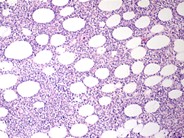

Webpathology.com: A Collection of Surgical Pathology Images

Webpathology.com: A Collection of Surgical Pathology Images from www.webpathology.com